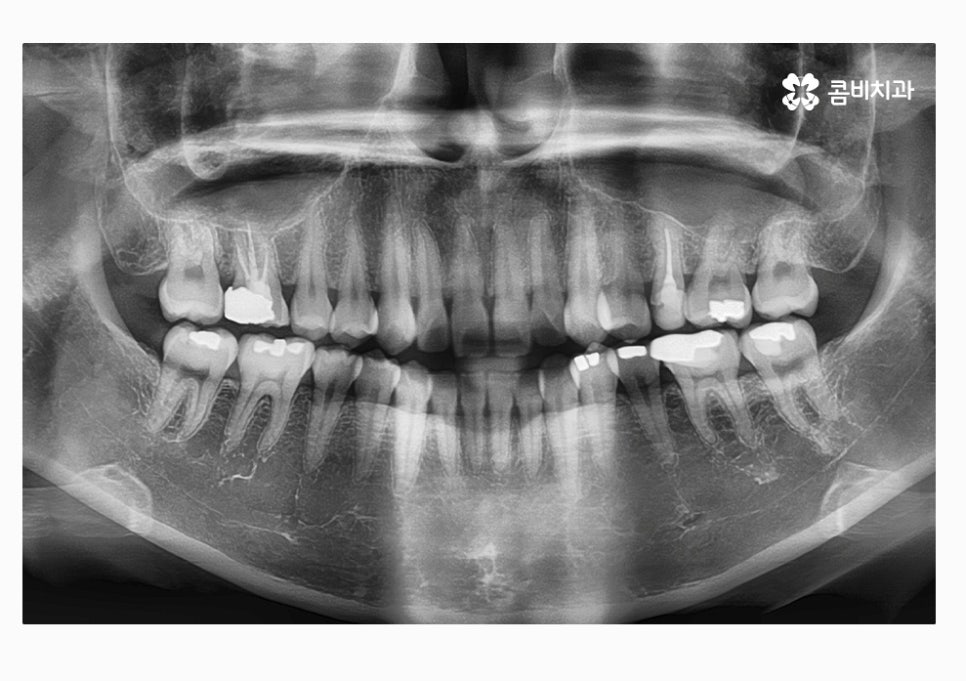

이번 케이스의 환자분의 경우에는 3급 부정교합과 절단교합을 치료하기 위해서

콤비교정을 시작하기 전에 발치를 먼저 진행하였는데

치아교정을 진행하면서 발치는 치아의 이동 공간을 확보하기

위한 목적으로 필요에 의해 선택적으로 진행될 수 있어요.

부정교합 환자분의 경우 부정교합의 원인이 치아 혹은 골격적인

부분인지 정확한 파악을 먼저 해야 하며 비발치, 비수술적인

방법으로 치료가 진행될 수도 있고 반대로 발치와 수술이 함께

병행될 수 있으니 치료 과정은 개인차가 있다고 볼 수 있는데요.